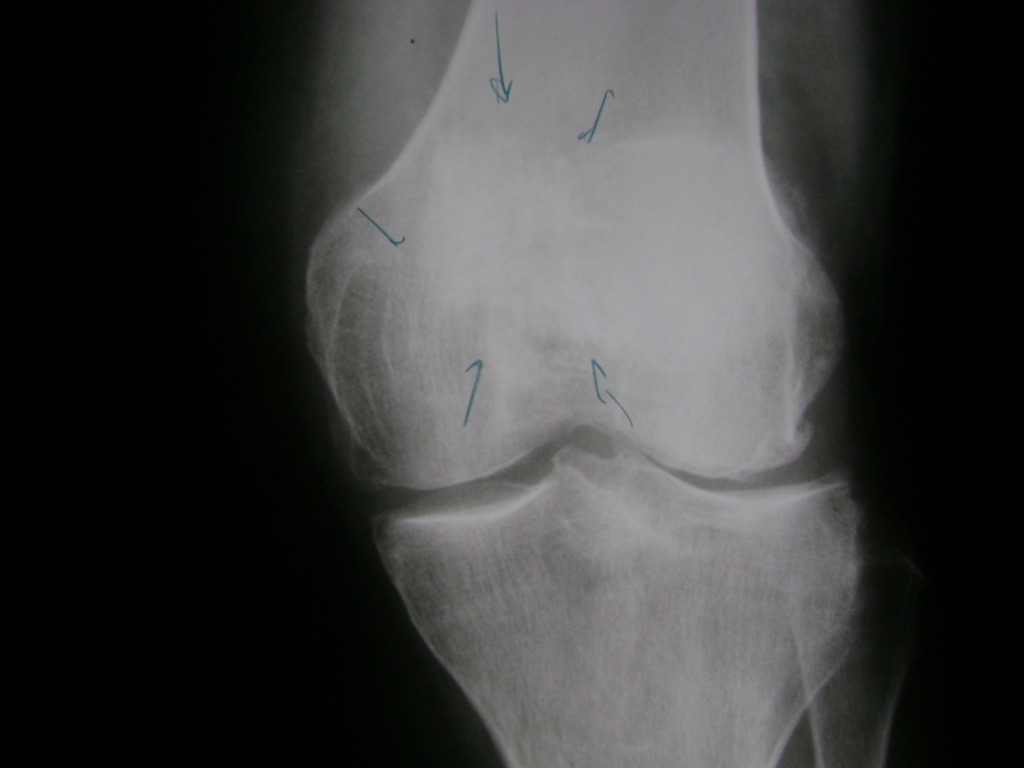

La artroscopia de rodilla es un cirugía en el cual la estructura interna de la articulación es examinada ya sea para realizar un diagnostico o para realizar un tratamiento, este procedimiento se realiza utilizando un instrumento parecido a un pequeño tubo llamado artroscopio.

La artroscopia se popularizo en 1960 y hoy en día es muy común en todo el mundo. Típicamente, es realizada por cirujanos ortopédicos de manera ambulatoria. Cuando se realiza de manera ambulatoria los pacientes pueden regresar a casa después de la operación, no se requiere quedarse en hospital.